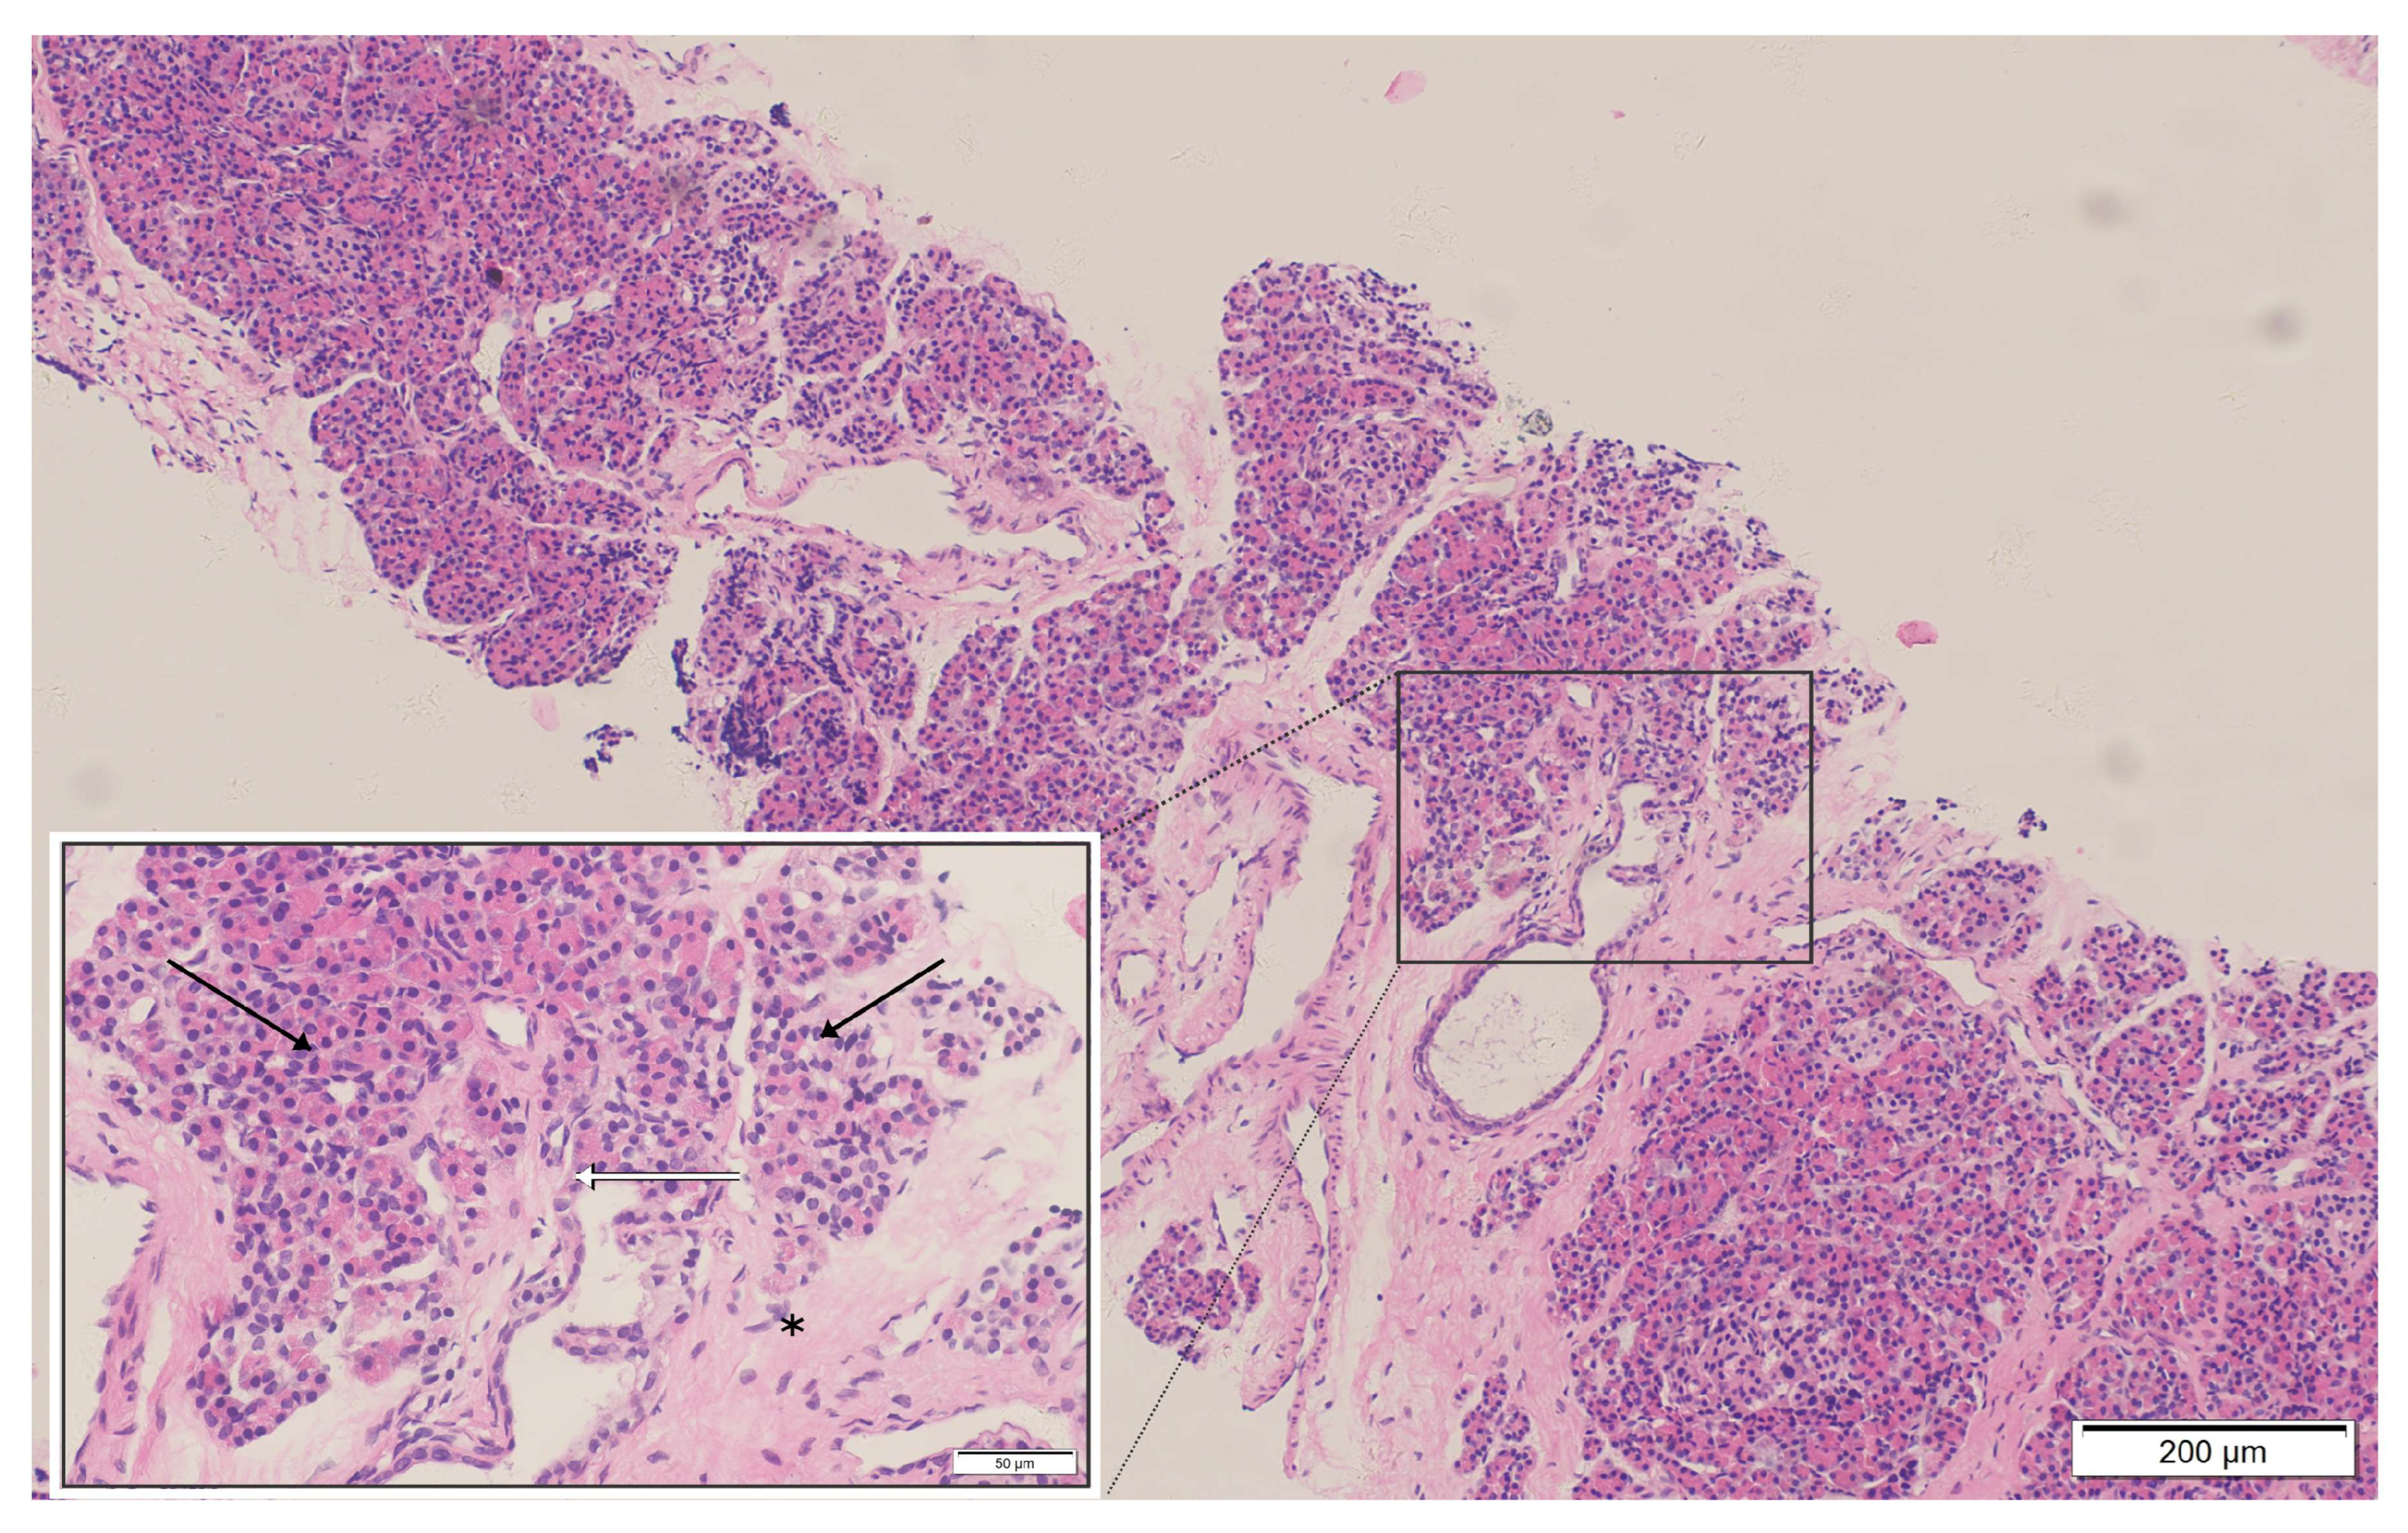

Figure 2.

Histopathological examination of the mediastinal mass biopsy (H&E stain): The specimen reveals pancreatic acinar structures with a lobular arrangement (black arrows), composed of tightly packed basophilic acinar cells with benign morphology. Scattered pancreatic duct-like structures are present (white arrows). The epithelial components are embedded in dense fibrous connective tissue exhibiting hyaline degeneration (asterisk). These findings are consistent with benign ectopic pancreatic tissue; no evidence of malignancy or lymphoma infiltration is identified.